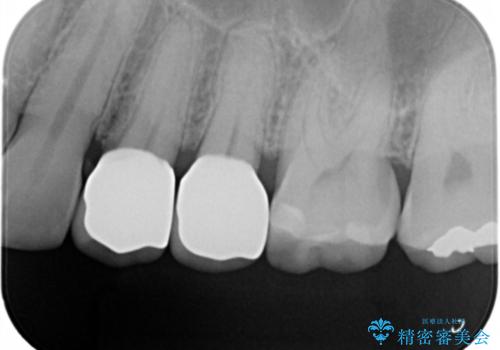

ジルコニアクラウンで治療を行いました。

- ジルコニアクラウン・仮歯 12.1万円×2費用は治療当時の料金となります

白い被せ物を入れたことにより銀が目立たなくなり

染みることもなくなりました。